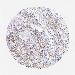

UROTHELIAL CANCER - Protein expressioni

A mouse-over function shows sample information and annotation data. Click on an image to view it in a full screen mode. Samples can be filtered based on level of antibody staining by selecting one or several of the following categories: high, medium, low and not detected. The assay and annotation is described here.

Antibody stainingi

Antibody staining in the annotated cell types in the current human tissue is reported as not detected, low, medium, or high, based on conventional immunohistochemistry profiling in selected tissues. This score is based on the combination of the staining intensity and fraction of stained cells.

Each image is clickable and will lead to virtual microscopy that enables deeper exploration of all samples and also displays staining intensity scores, fraction scores and subcellular localization as well as patient and tissue information for each sample.

Antibody CAB016119

Urothelial carcinoma, High grade

Urothelial carcinoma, Low grade

Adenocarcinoma, NOS